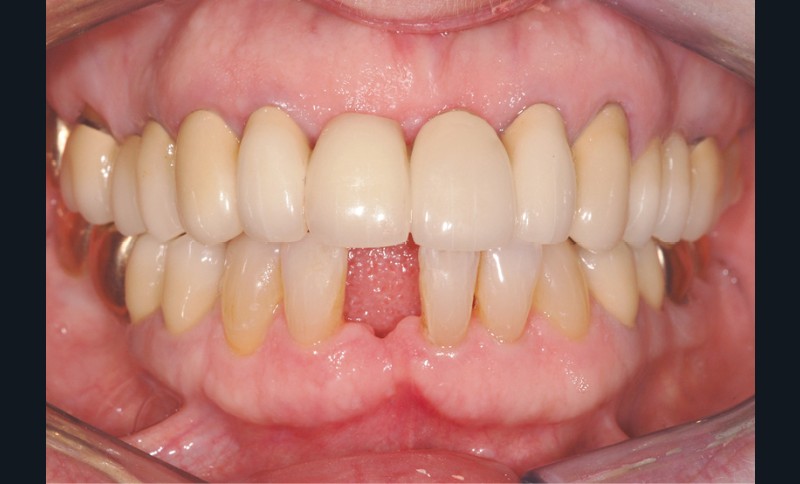

Le cas clinique présenté dans cet article traite de la gestion d’un édentement mandibulaire dans le secteur antérieur, survenu après un accident de la voie publique ayant entraîné une aggravation d’une lésion parodontale existante (fig. 1). Cette pathologie a nécessité l’extraction de la dent qui avait été traitée huit ans auparavant par une attelle-bridge en zircone, compte tenu de l’impossibilité médicale de mettre en place un implant (fig. 2).